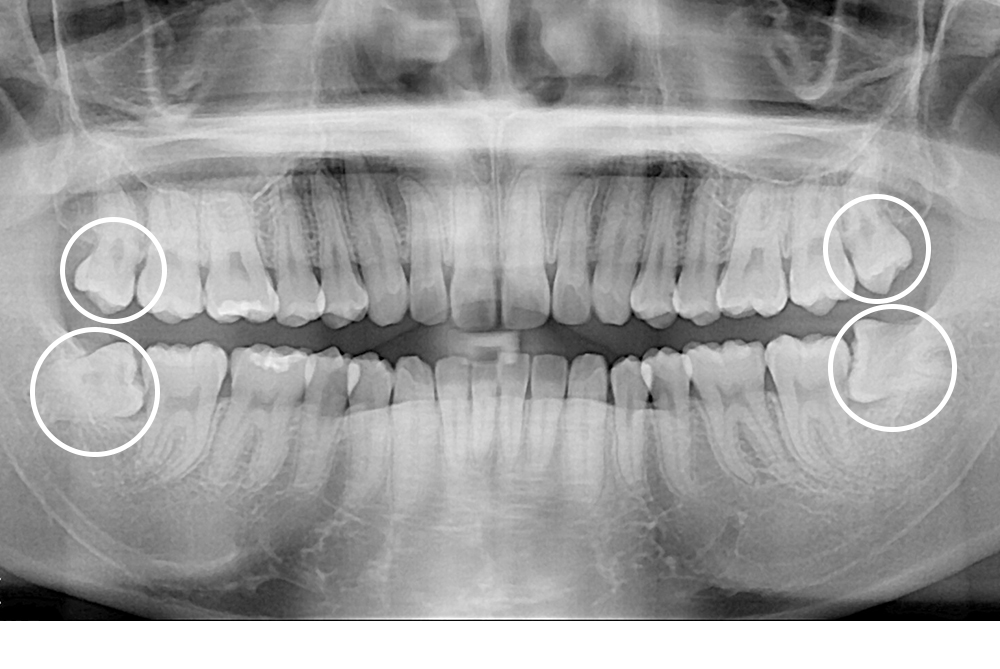

[사랑니] 매복 사랑니 발치

치료전 : 2019-08-07

세종치과는 구강악안면외과학 박사이신 원장님이 발치하는 치과입니다.